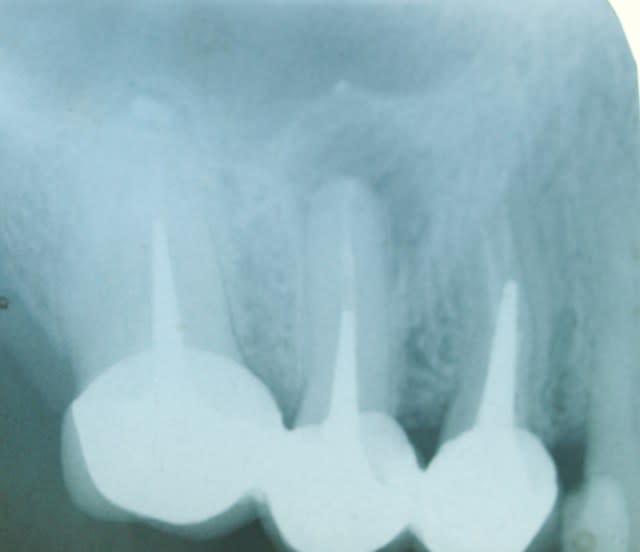

voila une belle indication

1 radio debut m1ld0f - Eugenol

2 depose  bridge p6o8dv - Eugenol

un indice important:

la patiente me dit qu ella a eu mal apres la pose des 3 dents alors que tout allait bien avant . les dents etaient deja devitalisées depuis longtemps...

l absces date de 6 mois.ça suinte tous les jours

vous pensez a quoi?

et a quel traitement ?